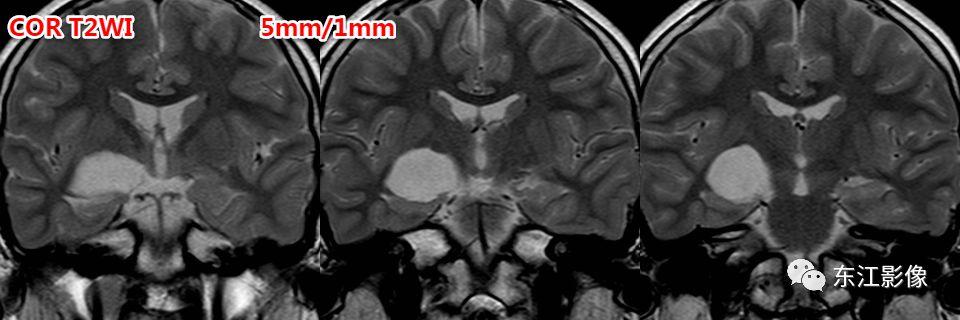

5. 脑脊液流动伪影

- 脑脊液流动伪影主要见于T2WI、FLAIR,主要是长TE序列容易出现流空效应的缘故。

- 但由于脑脊液流动方向、速率不一等因素的影响,呈现为非脑脊液信号影像,部分呈囊样。

- 常见于第三脑室、侧脑室室间孔旁区、脑干周围脑池(这些区域结构复杂)。

- 鉴别要点,T1WI、增强未能辨认;DWI与邻近一致的无信号;无占位效应。

侧脑室室间孔旁脑脊液流动伪影。

又一例。

桥前池脑脊液流动伪影。